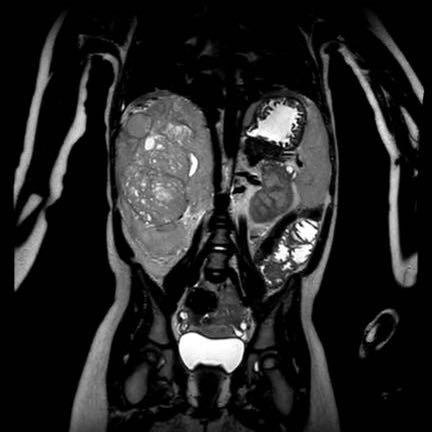

Ca lâm sàng 1

Hình ảnh chuỗi xung T2W mặt phẳng coronal cho thấy một khối u không đồng nhất ở thận trái với các thành phần nang nhỏ.

Khối u ngấm thuốc kém hơn so với phần nhu mô thận bình thường còn lại ở ngoại vi.

Các thành phần đặc của khối u cho thấy hạn chế khuếch tán rõ rệt (mũi tên).

Đây là u Wilms ở bé trai năm tuổi. Hóa trị tiền phẫu được thực hiện theo phác đồ Umbrella của SIOP-RTSG, sau đó tiến hành cắt thận.